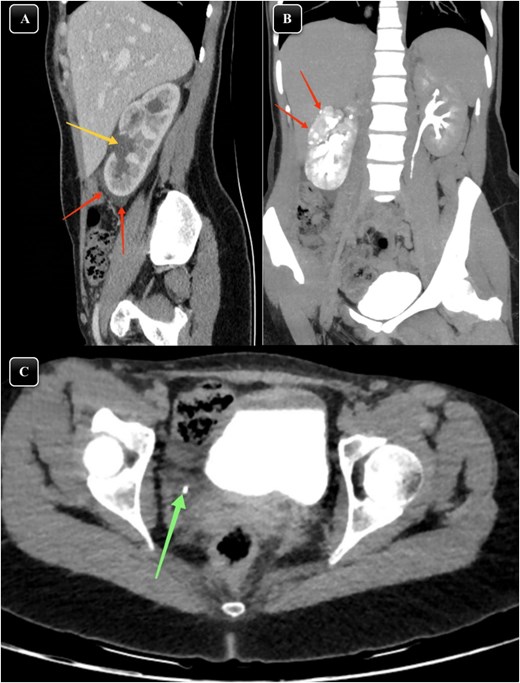

Given the patient's symptoms, an urgent abdominal ultrasound was performed, which demonstrated moderate right-sided hydroureteronephrosis with perinephric-free fluid. Both kidneys appeared normal in size, shape, echostructure, and position. As a result, a contrast-enhanced CT scan of the abdomen and pelvis was performed, revealing an enlarged and edematous right kidney with moderate hydroureteronephrosis. A 3 mm distal ureteric stone was identified ~1.5 cm proximal to the vesicoureteric junction (Fig. 1). Moreover, significant perinephric and periureteral fluid and fat stranding were also noted (Fig. 1). Additionally, there was evidence of partially delayed calyceal contrast excretion with extravasation but no pelvic or ureteric excretion 20 minutes post-contrast injection (Fig. 1). These clinical and imaging findings were highly suggestive of renal calyceal rupture secondary to ureteric obstruction.

(A) Sagittal section of a contrasted CT scan obtained at the venous phase showing moderate right hydronephrosis (arrow) with perinephric free fluid and fat stranding (arrow). (B) MIP reconstructed coronal images of contrasted CT scans obtained at delayed phases showing delayed renal excretion of the right kidney with minimal contrast extravasation out of the pelvicalyceal system (arrows). (C) Axial section of contrasted CT scan showing distal right ureteric stone about 1.5 cm away from vesicoureteric junction (arrow) surrounded by minimal fat stranding and fluid.